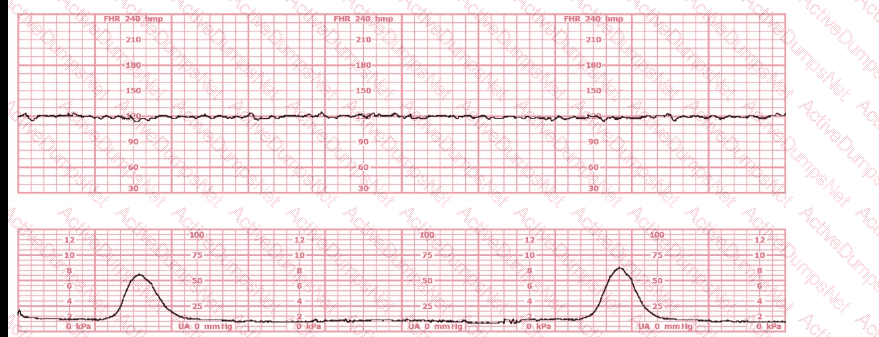

A woman at 38-weeks gestation is admitted to labor and delivery following a fall down the stairs three hours ago. She started feeling contractions in the ambulance. The fetal heart rate tracing shown is on initial evaluation and represents 25 minutes. This tracing is most consistent with a